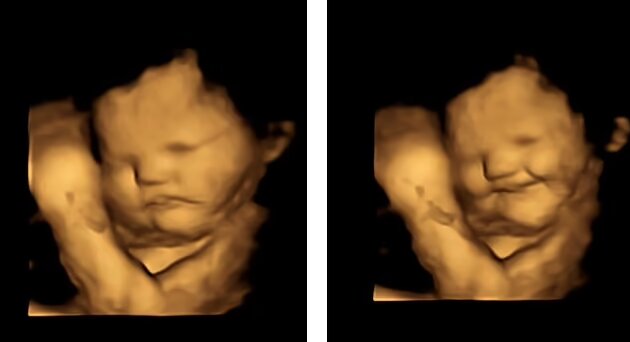

نتایج این پژوهش نشان داد که جنینها بلافاصله پس از خوردن هویج توسط مادرشان، لبخند میزنند اما وقتی مادرها کلمبرگ را خوردند، واکنشی حاکی از انزجار نشان دادند.

هنگامی که زنان هویج مصرف کردند، جنینها در اسکن لبخند زده بودند اما زمانی که آنها کپسول کلمبرگ را مصرف کردند، جنینها انزجار را در چهره خود نشان دادند.